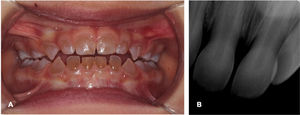

Presentamos el caso de un varón de 7meses derivado a la consulta de odontología pediátrica por el pediatra de cabecera por la decoloración amarillenta y apariencia translúcida ambarina de los dientes temporales (fig. 1A). Las radiografías periapicales mostraron la obliteración de dos tercios de las cámaras pulpares sin alteraciones apreciables en el grosor del esmalte, la estructura de la corona o el tamaño de las raíces (fig. 1B). El estudio de los antecedentes familiares reveló anomalías dentales similares en el padre, la abuela paterna, un tío abuelo paterno y la bisabuela paterna del paciente (fig. 2). La secuenciación del gen DSPP en el paciente detectó una nueva variante probablemente patogénica [c.3047del p.(Ser1016llefs*298)] que podría explicar el caso presentado.